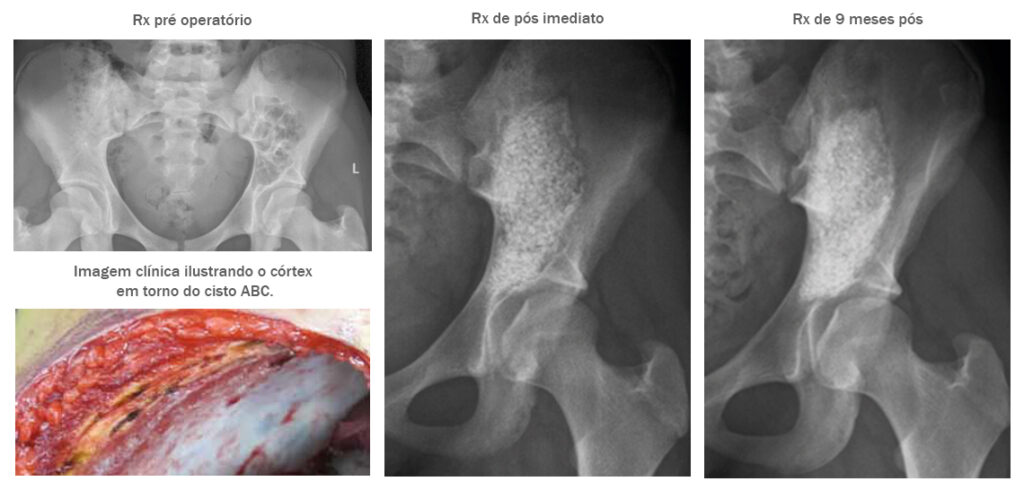

Paciente: Menina de 15 anos com um grande cisto ósseo aneurismático na região pélvica.

Procedimento: O cisto ósseo foi enucleado, o defeito foi fenolizado e preenchido com 60 cc/2.0-3.15 mm de BonAlive® granules.

Evolução Clínica: Aos 9 meses de pós operatório a paciente estava totalmente curada e livre de qualquer sinal de recorrência do cisto.